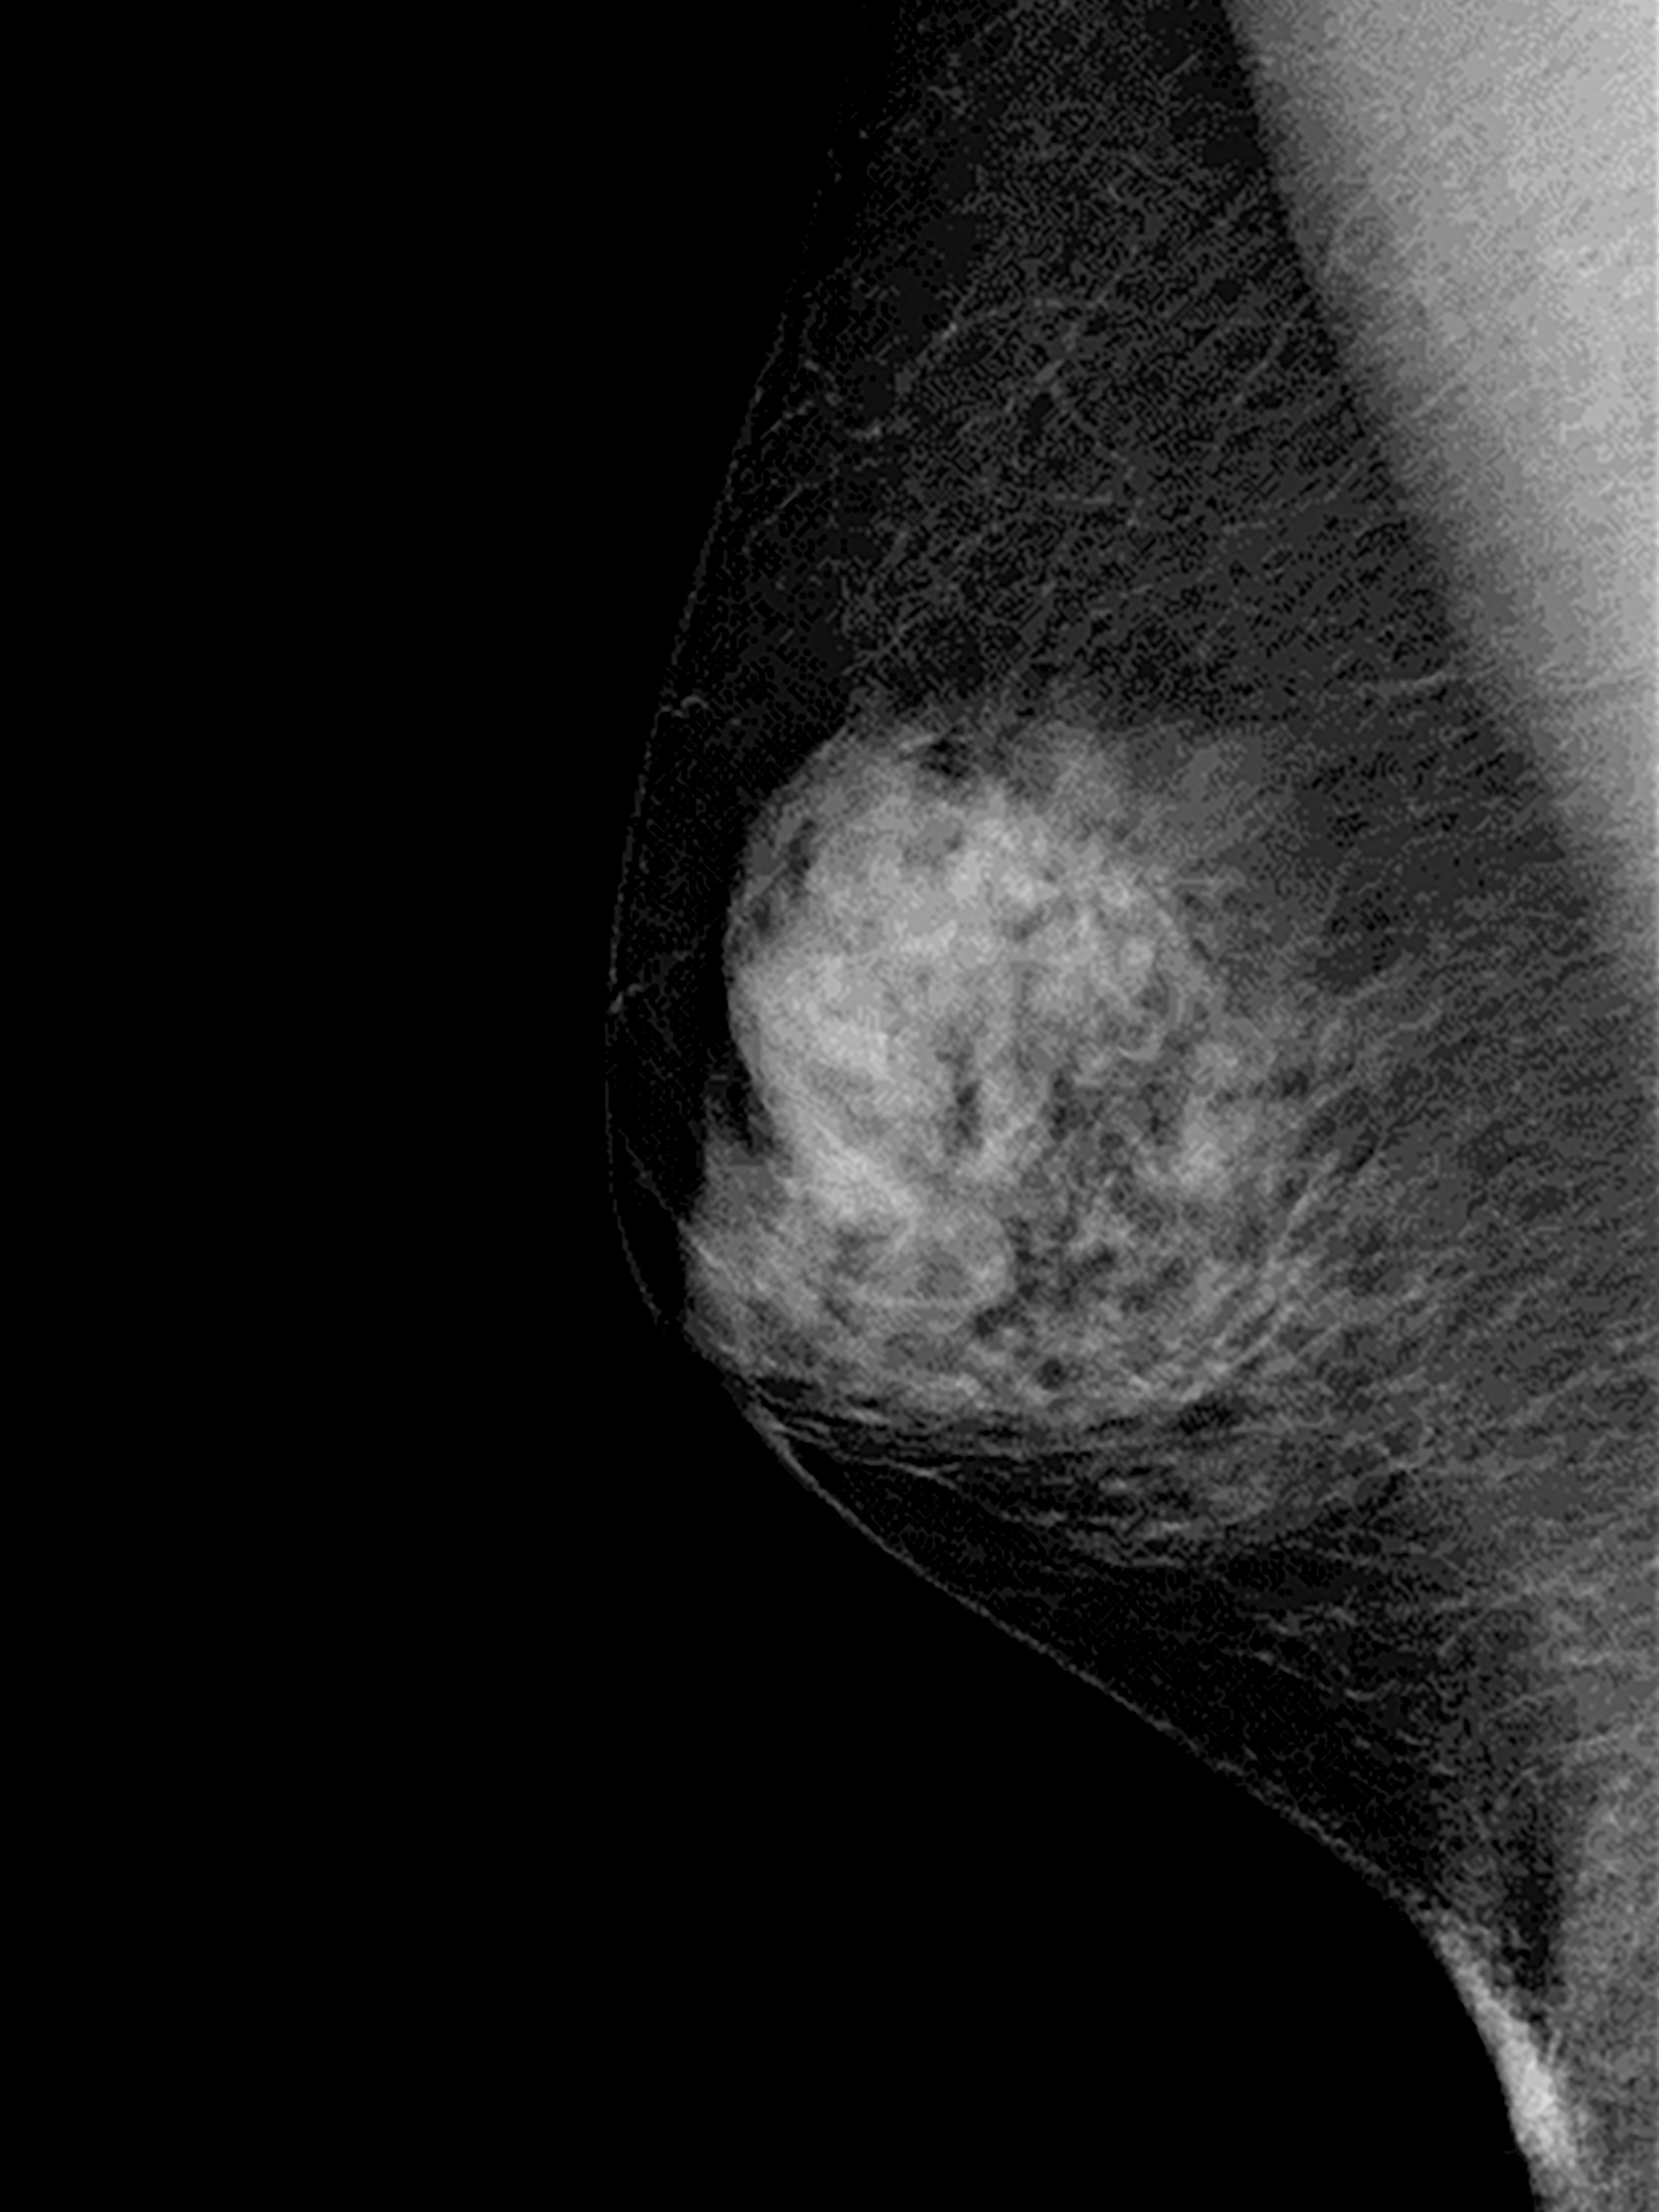

X線乳房撮影装置

マンモグラフィ検査とも呼ばれ、触診でもわからない小さな腫瘍や微細な石灰化を描出することができるため、早期の乳がんを発見することができます。

病変をよりわかりやすく描出するために、乳房を均一の厚さに圧迫して検査します。

エコー検査と併用することで、更に診断価値の高い検査となります。